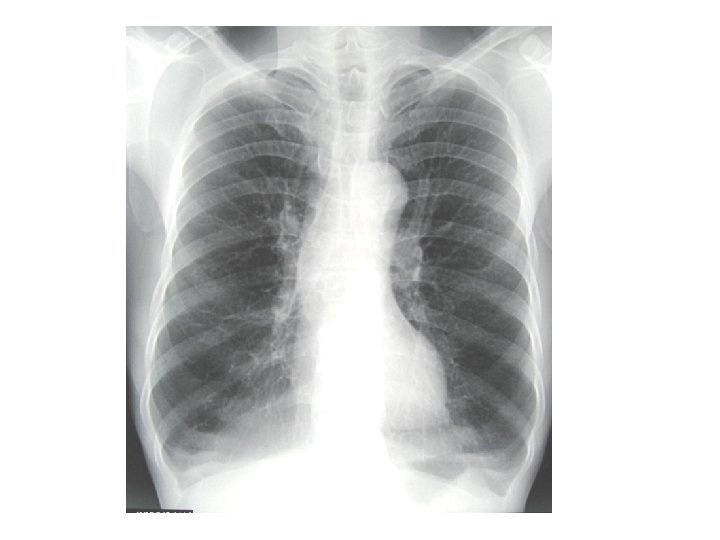

BÖnh ¸n l©m sµng • C©u hái 1: theo Anh (chÞ) th× bÖnh nh©n cã thÓ bÞ bÖnh g×? Anh (chÞ) h·y ph©n tÝch c¸c yÕu tè l©m sµng ®Ó cñng cè chÈn ®o¸n cña m×nh • C©u hái 2: theo Anh (chÞ) xÐt nghiÖm cËn l©m sµng nµo cÇn lµm? T¹i sao? • C©u hái 3: H·y m « t¶ h×nh ¶nh x quang phæi cña bÖnh nh©n nµy.

BÖnh ¸n l©m sµng • C©u hái 1: H·y m « t¶ h×nh ¶nh x quang cña bÖnh nh©n nµy ? • C©u hái 2: H·y cho biÕt chÈn ®o¸n cña anh (chÞ) ? • C©u hái 3: H·y cho biÕt nh÷ng dÊu hiÖu nÆng cña bÖnh?